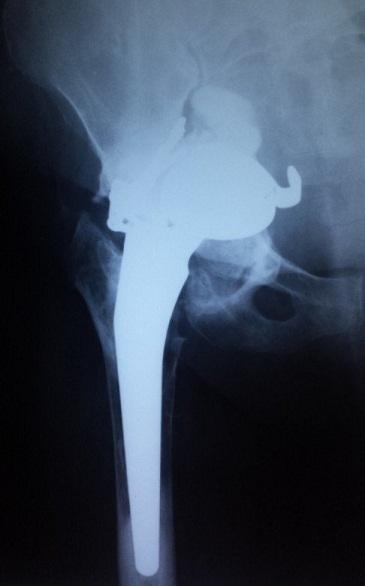

[Compression of the external iliac artery by Kerboull frame: report of a case].

Pan Afr Med J. 2015 Nov 18;22:251. doi: 10.11604/pamj.2015.22.251.7566. eCollection 2015.